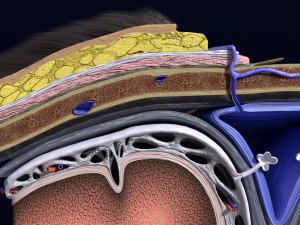

Brain with meninges scalp detailed labelled 3D 3D मॉडल

A blend model of brain along with its covering layers (meninges), skull bone and scalp labelled in detail and anatomically precise. The parts depicted are white, gray, pia, arachnoid, dura, bone, skin, fat, aponeurosis, periosteum, falx cerebri and more.

The material is high resolution image textures and normal maps based on non overlapping UVs. The texture and normal maps are packed with the blend file itself.